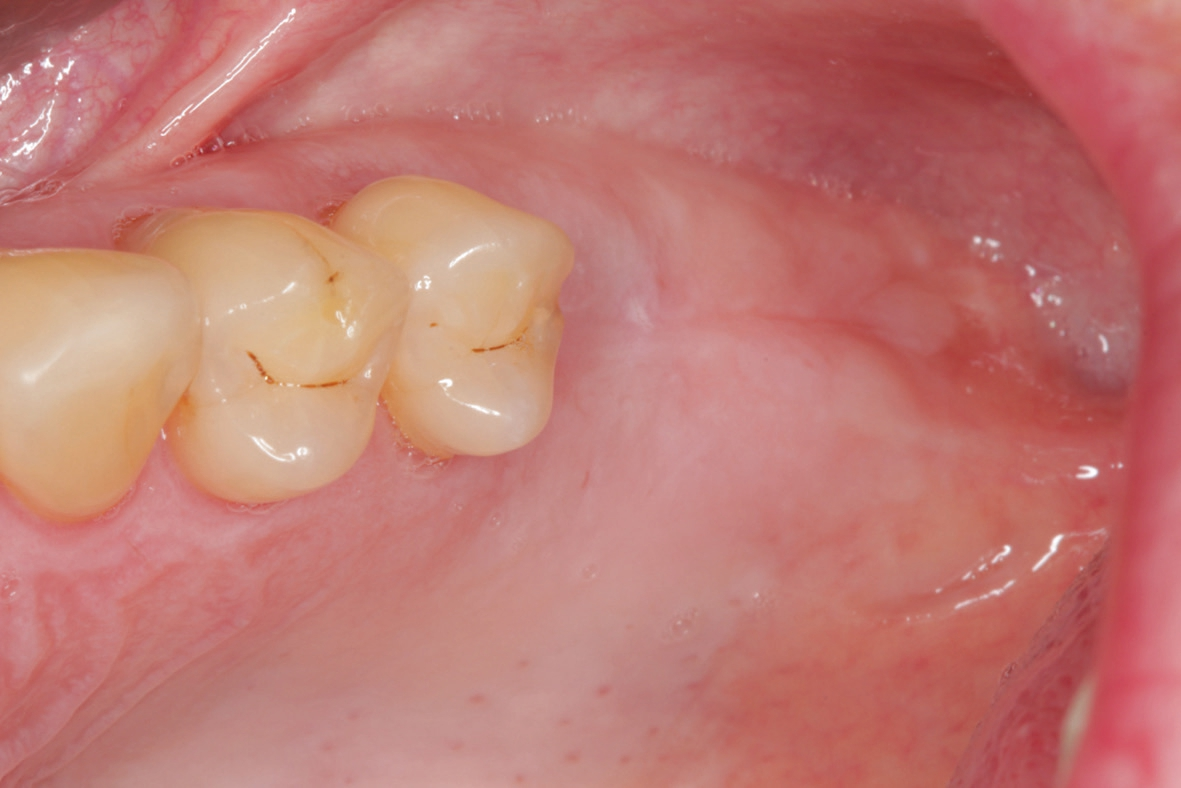

60-jähriger, männlicher Patient mit seit etwa acht Jahren bestehender Freiendsituation in regio 26/27. Drei Jahre zuvor wurde auf Position 36 ein PURE Monotype erfolgreich eingesetzt und prothetisch versorgt. Insgesamt ausgezeichnete Mundhygiene und absolut reizfreie Situation an 36. Der Wunsch des Patienten war nun die Versorgung der Position 26 mittels eines Keramikimplantates ohne größere chirurgische Intervention. Nach Anfertigung der dreidimensionalen Aufnahme (DVT) stellten sich ein ausreichendes transversales Knochenangebot und eine vertikale Höhe von ca. 5 – 6 mm zur Kieferhöhle dar, so dass ein interner Sinuslift und die Verwendung eines zweiteiligen Implantates geplant wurden. Das geringe vertikale Knochenangebot und die reduzierte Qualität verglichen mit dem Unterkiefer hätten bei Verwendung eines einteiligen Implantates mit transgingivaler Heilung ein Risiko für die erfolgreiche Osseointegration dargestellt. Zur Vorbereitung wurde die leichte basale Schleimhautschwellung beim Hals-Nasen-Ohren Arzt abgeklärt und der Patient führte täglich Nasenspülungen durch.

Nach lokaler Anästhesie wurden ein Kieferkammschnitt und eine nur minimale Mobilisation des Mucoperiostlappens durchgeführt. Beim internen Sinuslift nach Summers wird die Pilotbohrung bis ca. 1 mm vor die Begrenzung der Kieferhöhle vorgenommen und je nach Knochenangebot und Qualität mittels verschiedener Osteotome (Institut Straumann) weiter aufbereitet. Unabdingbar ist dabei die regelmäßige Kontrolle der Unversehrtheit der Schneider‘schen Membran durch einen „Nasenblasversuch“. Nach erfolgreicher Aufbereitung des Lagers konnte ein Implantat Größe 4,1/10 mm sehr gut primärstabil inseriert werden, anschließend primärer Wundverschluss mittels 5/0 monophiler Naht. Nach vier Monaten erfolgte die minimalinvasive Freilegung und Applikation des Gingivaformers.